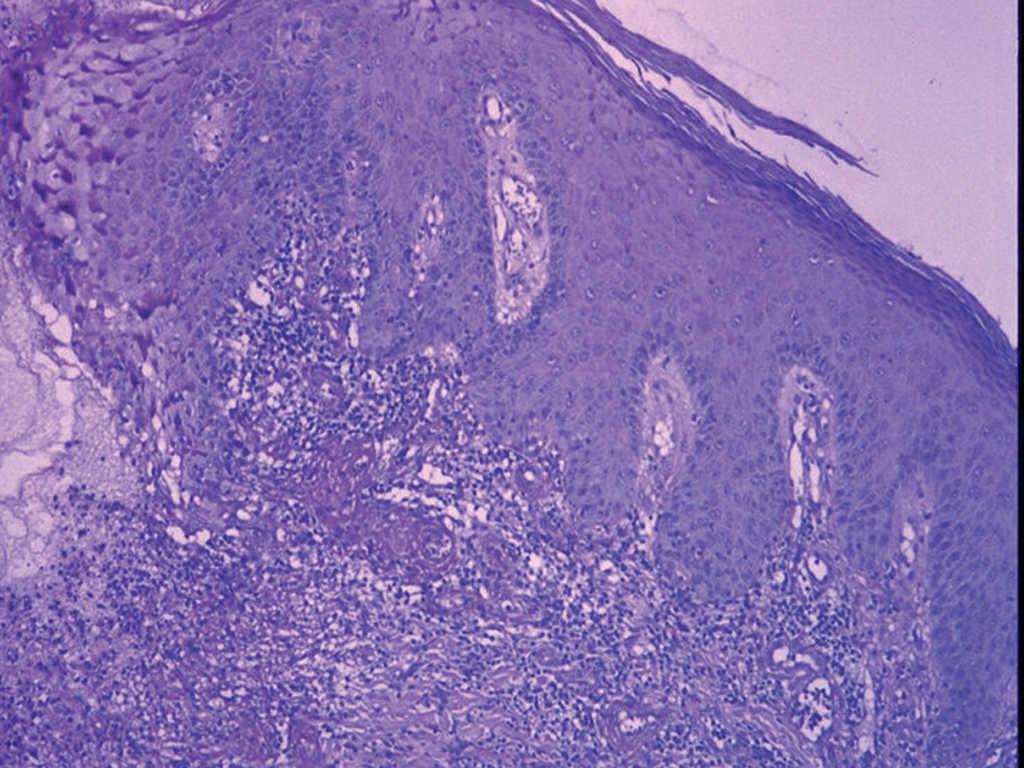

Un varón de 23 años, con antecedentes de dermatitis atópica y pie cavo bilateral corregido quirúrgicamente presentó un antecedente de un Mantoux positivo en 1995. En ese momento se instauró quimioprofilaxis con isoniazida, pero se tuvo que suspender al cabo de pocas semanas debido a una elevación grave de las transaminasas. El paciente presentó en 1999, un exantema varioliforme en la cara anterior de ambos miembros que se diagnosticó de foliculitis y fue tratado con doxiciclina con mejoría moderada. Al cabo de 9 meses presentó un episodio similar, pero en esta ocasión la evolución fue desfavorable, por lo que se remitió a nuestro servicio. En la primera consulta dermatológica se apreciaba una erupción diseminada, más o menos simétrica en miembros, con lesiones polievolutivas, pápulas, pústulas, escaras y cicatrices (fig. 1). La biopsia cutánea mostró una vasculitis granulomatosa necrosante (fig. 2), con focos granulomatosos con células gigantes (fig. 3). El cultivo micológico y bacteriológico de exudado y de material de biopsia fue negativo. La tinción de Ziehl fue negativa. La radiografía de tórax no mostró hallazgos patológicos. La bioquímica mostró una elevación moderada de las transaminasas. Finalmente, la PCR para micobacterias sobre material de biopsia resultó negativa. La prueba de Mantoux resultó necrótica. Se inició tratamiento con isoniazida 300 mg/día. A los 3 meses se suspendió el tratamiento por una elevación de transaminasas de cuatro veces sobre los valores básicos. En ese momento, la mejoría del cuadro había sido completa, y sólo se habían observado cicatrices varioliformes residuales en las piernas y las nalgas. En la última revisión de 2005 persistían las marcadas cicatrices residuales sin signos de actividad lesional reciente.

Fig. 2.--Semicuña de necrosis dermoepidérmica, con vasculitis periférica e infiltrado linfohistiocitario masivo. (Hematoxilina-eosina, x200.)